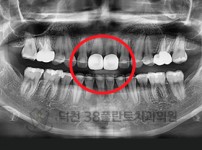

치료전후